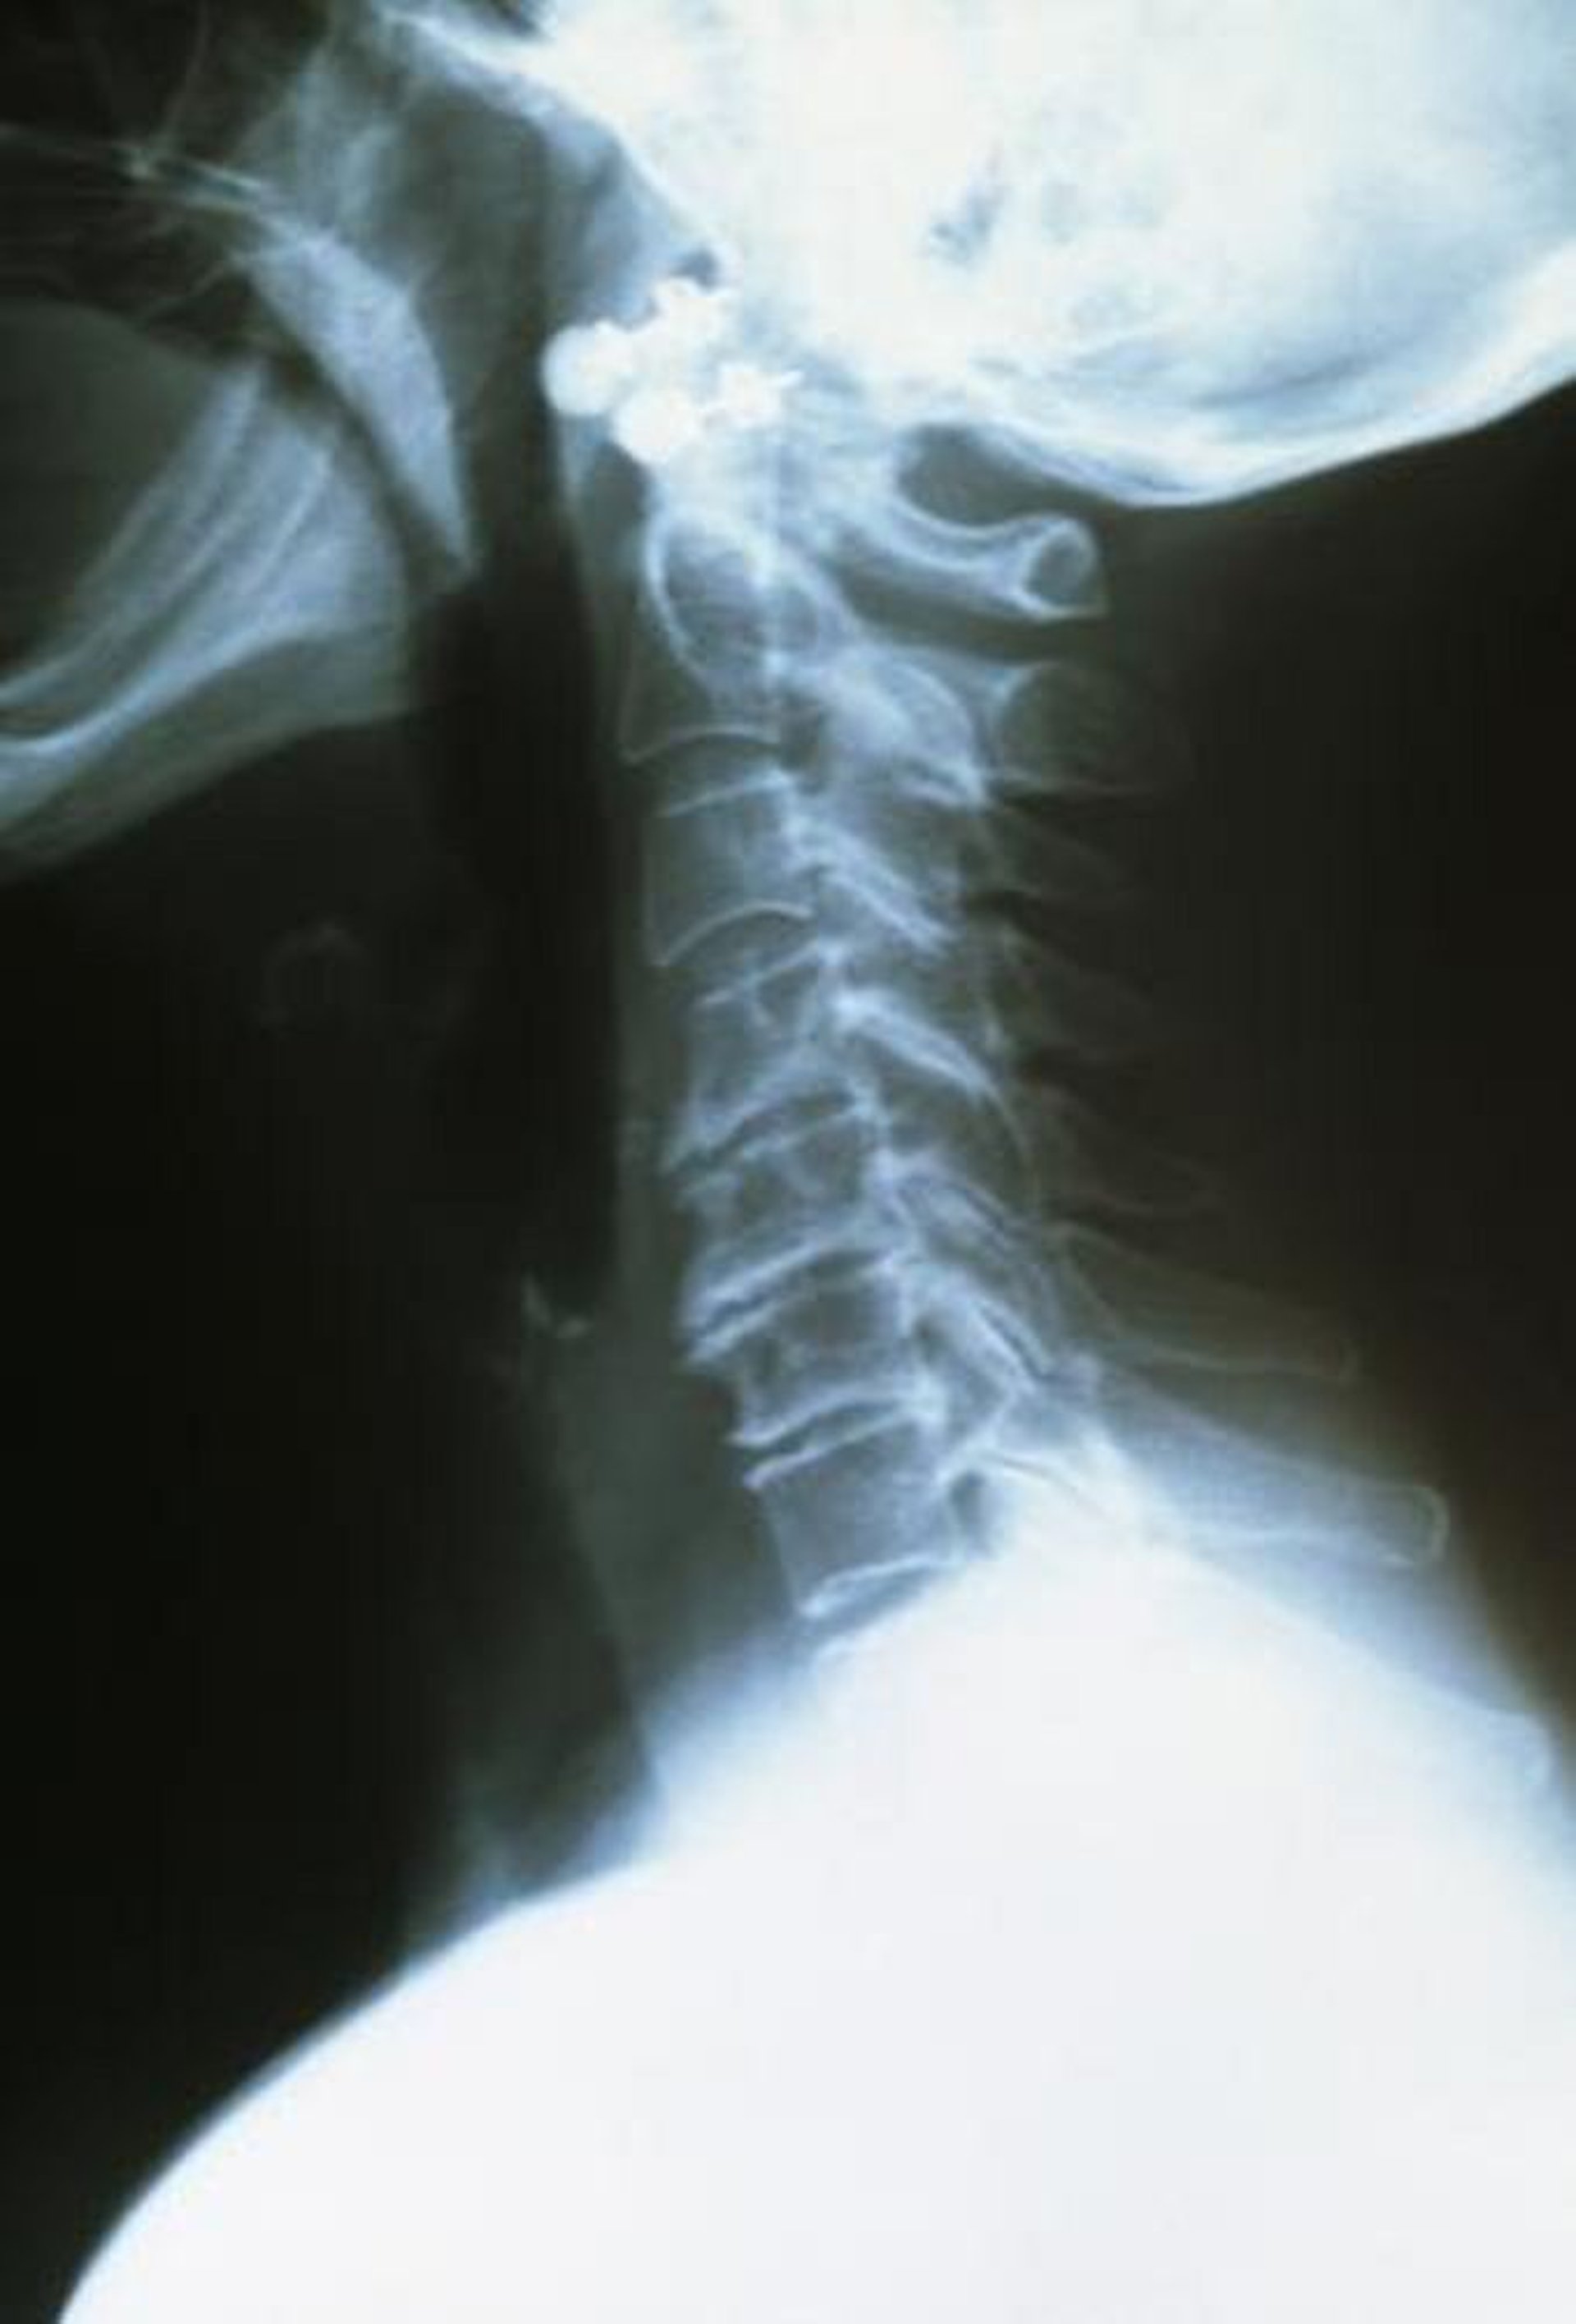

Остеоартроз шейного отдела позвоночника

Верхние шейные позвонки здоровы, хорошо удалены друг от друга и имеют цельные края. Нижние позвонки, пораженные артритом, ближе друг к другу и имеют грубые и неровные края.